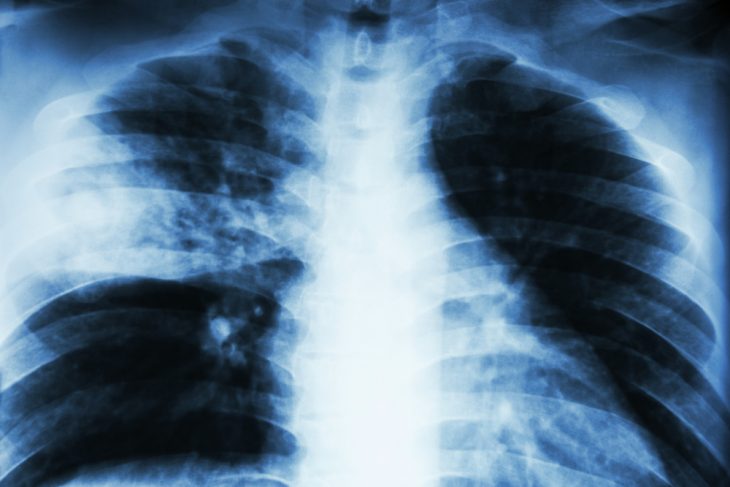

Главным методом, позволяющим достоверно определить, есть ли у больного пневмония, является рентгенография органов грудной клетки. Для постановки точного диагноза данное исследование должно быть проведено в 2 проекциях – прямой и боковой. При анализе рентгенограммы специалист оценивает объем, характер, однородность поражения ткани легких, характеристики плевры. В первые часы заболевания в области поражения определяется лишь усиление легочного рисунка, однако по мере развития болезни появляются очаговые (диаметром до нескольких сантиметров) и более крупные – занимающие всю долю или даже несколько долей с одной или обеих сторон – затемнения.